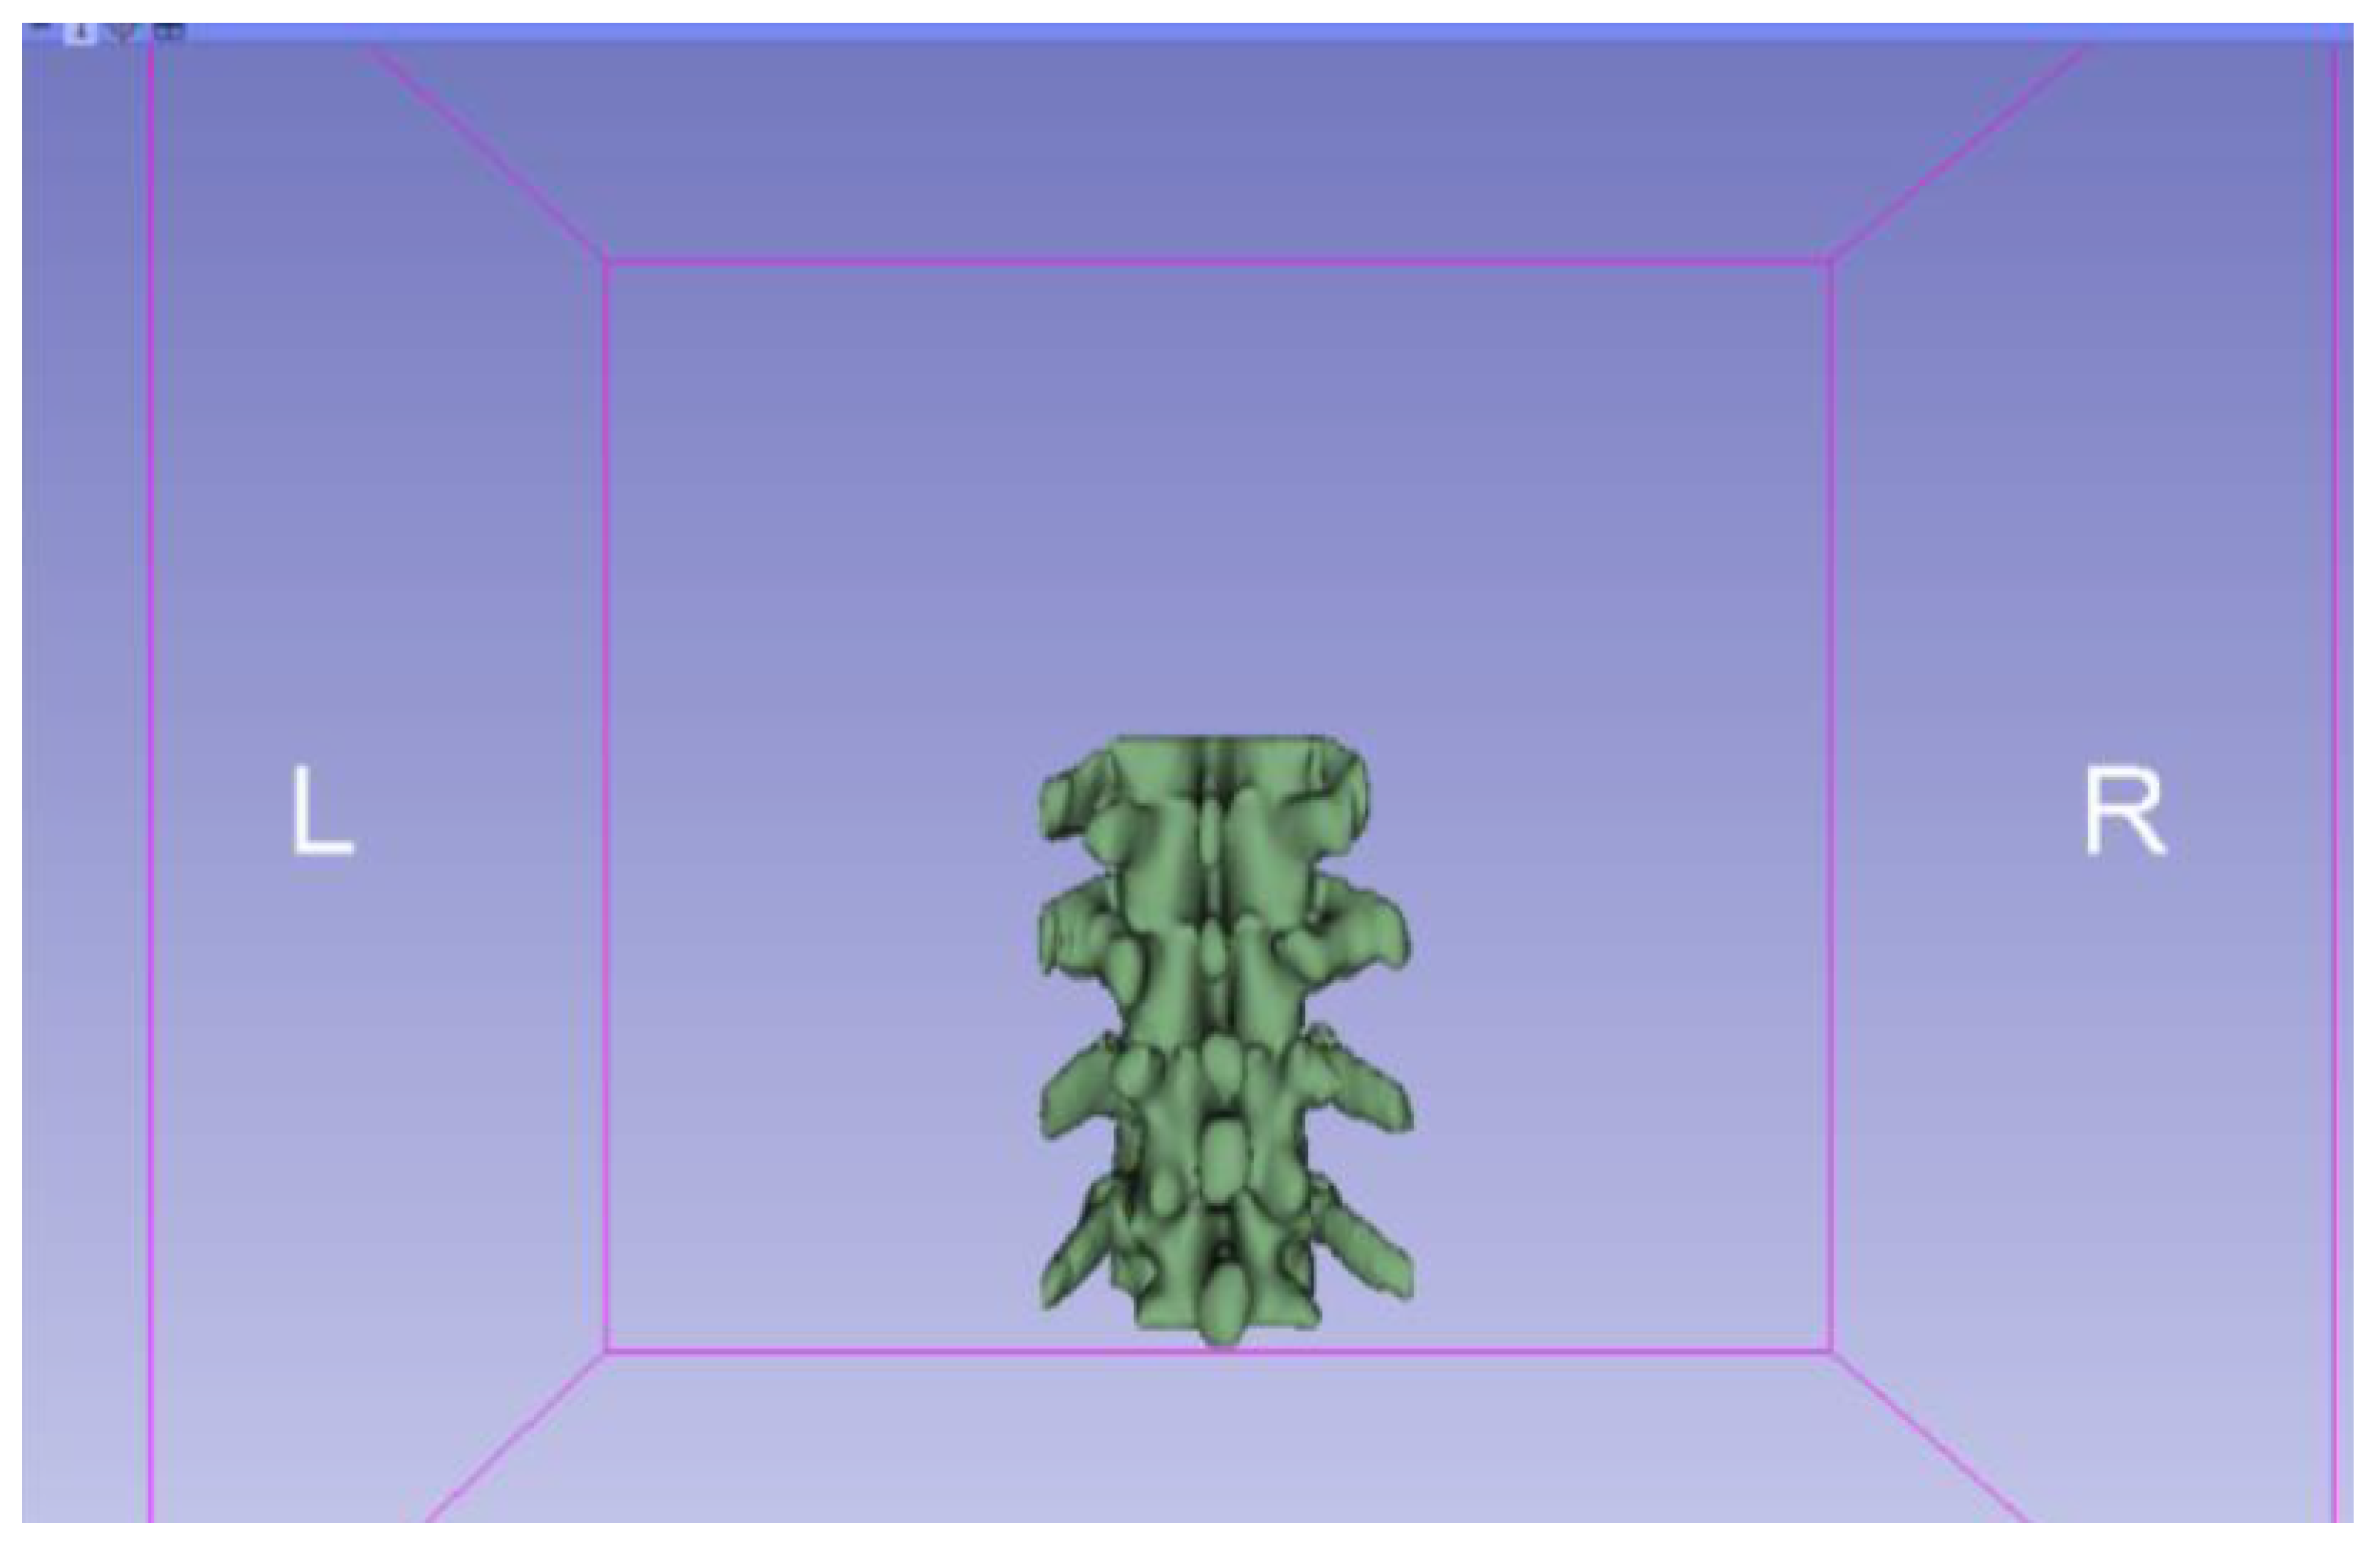

3.1.1. DICOM-to-STL File

| Vertebrae | [150, 300] | Median | 0.8 | 0.18 | 25 |